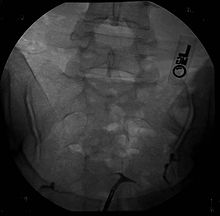

Hysterosalpingography of a T shaped uterus